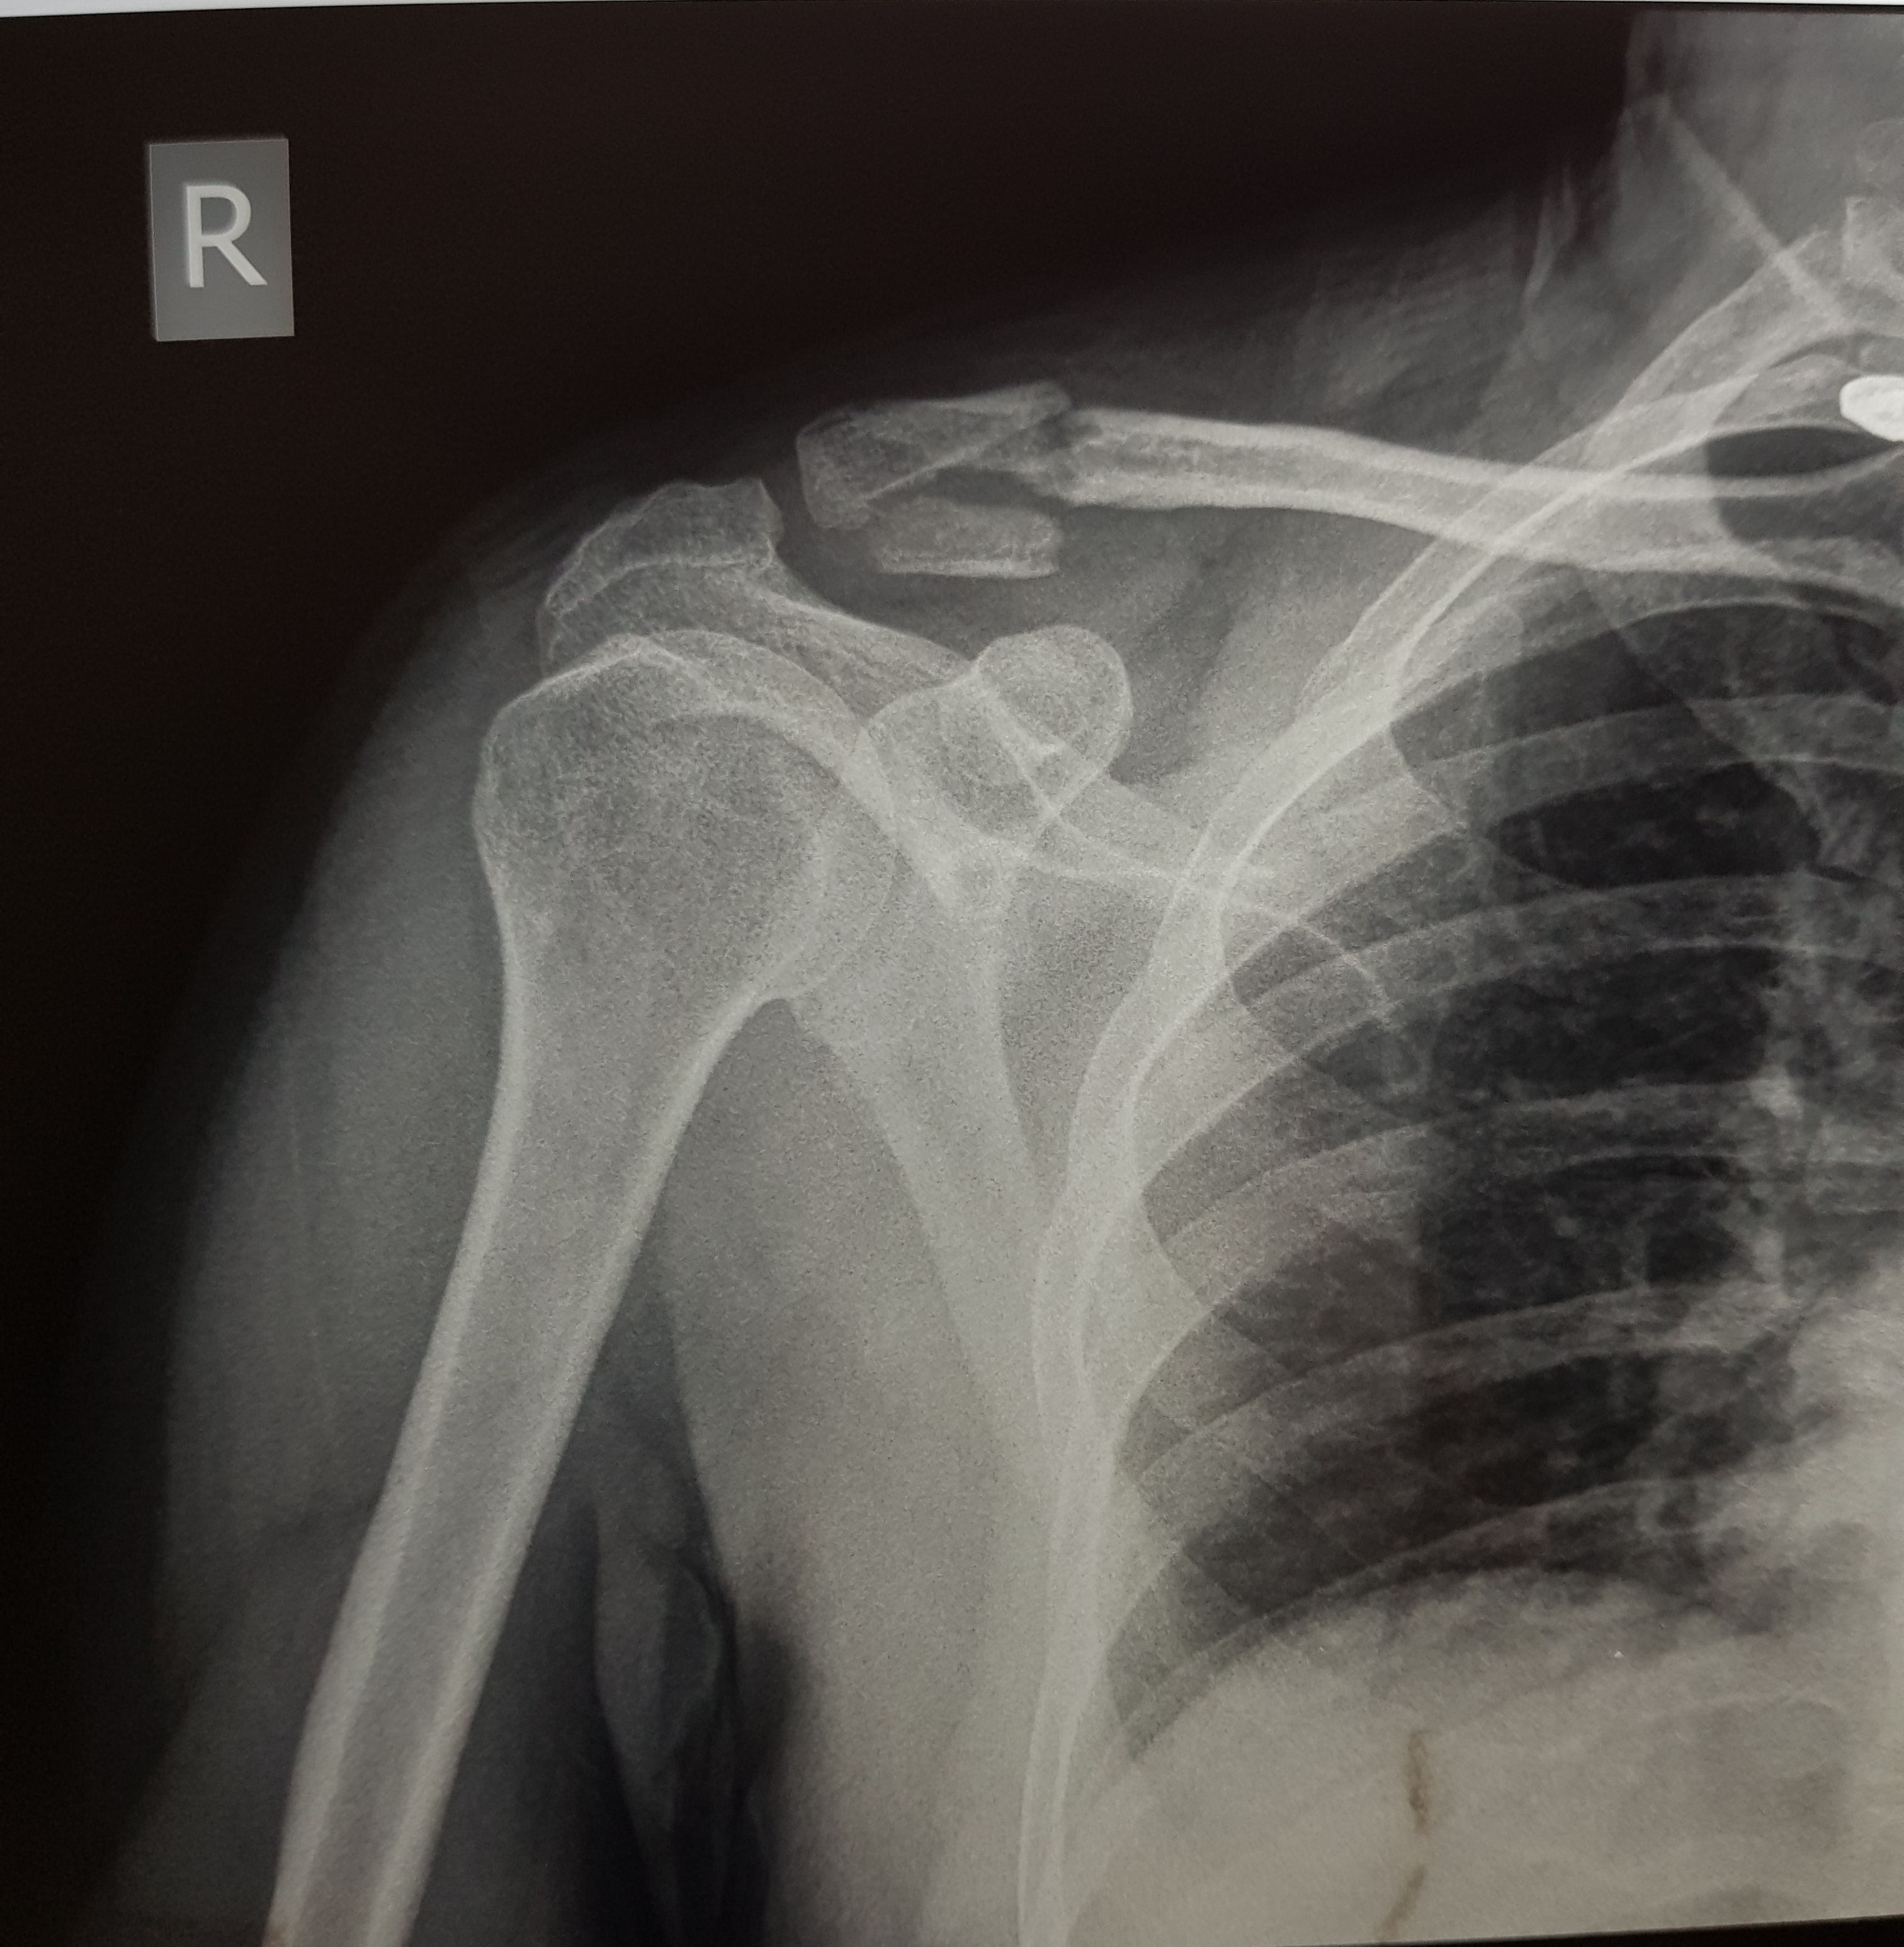

Please have a look at the fracture and inform what is the best treatment for recovery. currently he is wearing a sling arm to immobilize his shoulder. No POP or surgery done. it happened 2 days ago

Sling is fine. No surgery required if there is no open wound or any other

injury.

This need surgery

Thanks

Tariq Sohail

Treat it non operatively ,with cuff and collar sling

For this fracture best is surgery